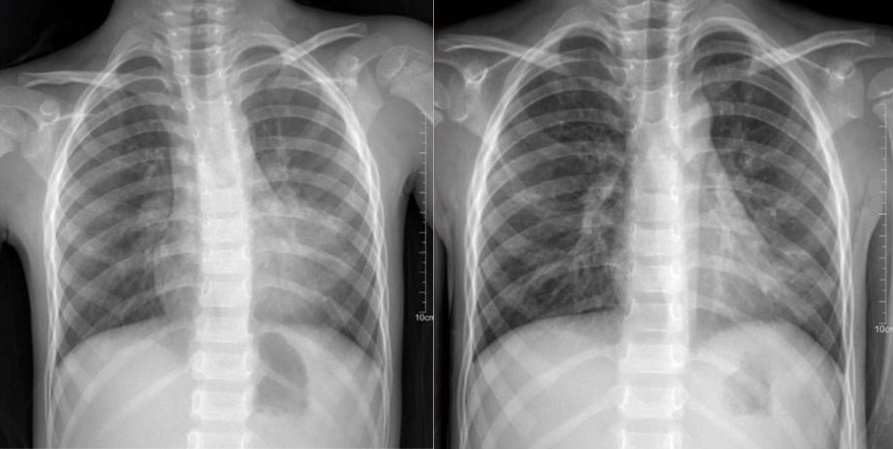

Hình chụp Xquang phổi trước và sau điều trị

Song song đó, tình trạng viêm phổi cũng được kiểm soát tốt. Bé K. hồng hào, ăn uống tốt và được xuất viện trong niềm hạnh phúc của gia đình.